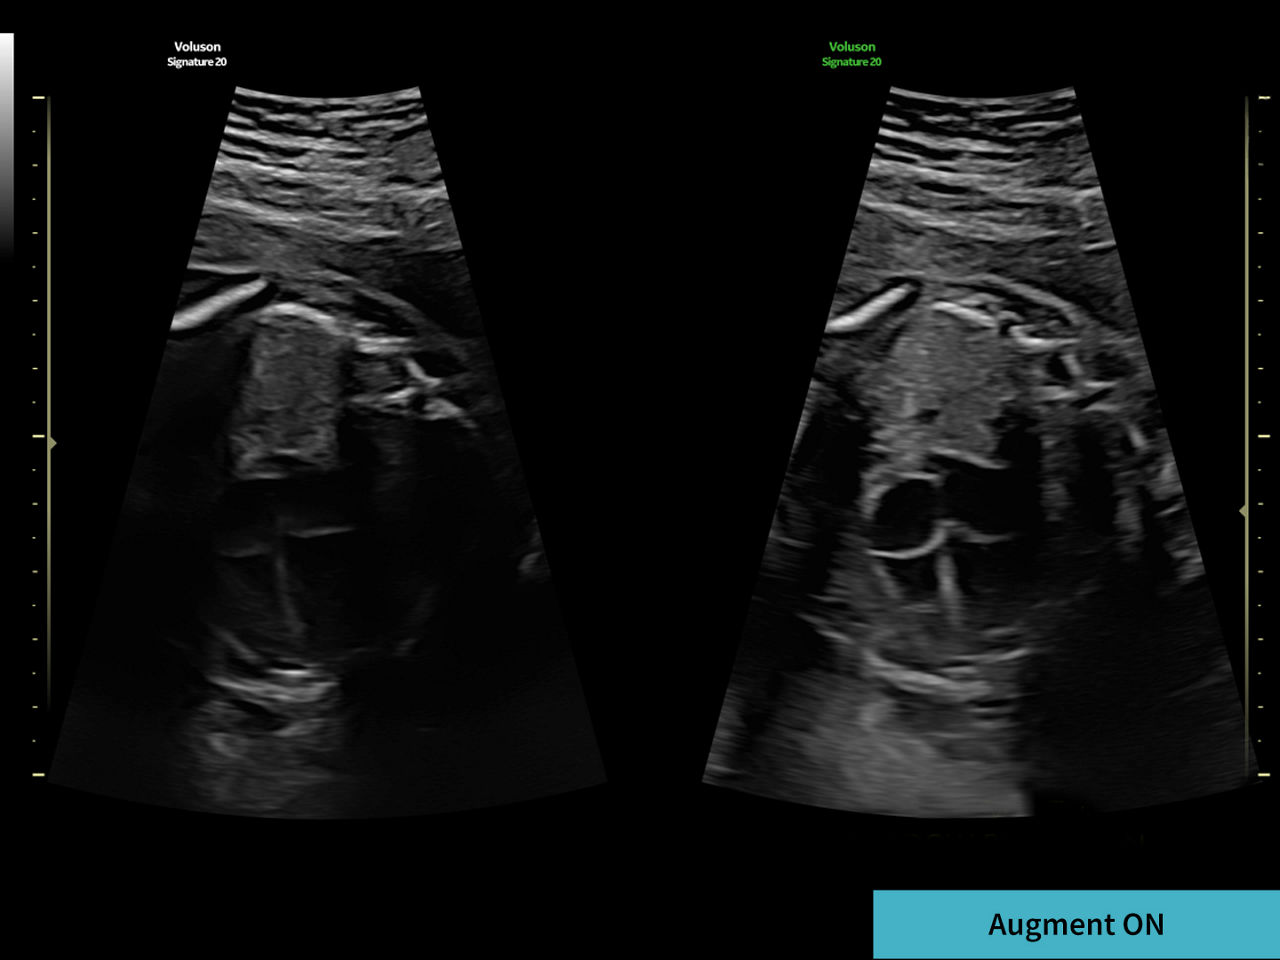

Restore tissue information and borders

Decreases shadows on B-mode imaging which can obscure adjacent structures by helping to restore tissue information and borders.

3-augment-image